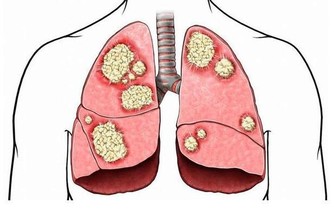

假如這個部位沒有及時清潔乾淨,牙菌斑的隊伍就會越積越壯大,形成牙結石;有了牙結石這一口原材料,牙齦便有膨脹成為暴發戶的資本,接著牙齦發炎出血,敏感萎縮就是憑證,可大家不明真相的情況下又更加避開刷牙齦,如此形成一個惡性循環,導致口腔衛生越來越差。